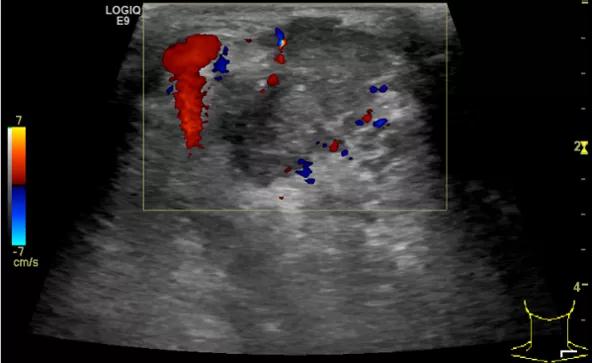

第三例是甲状腺癌患者,双侧甲状腺癌切除术后、碘治疗后一年余效果欠佳,超声显示左颈3区3枚低回声结节,穿刺示甲状腺乳头状癌转移。患者不愿意手术,希望采取局部治疗。对病灶进行液体隔离后采取热消融术,由于淋巴结较小,热消融一分钟左右完全灭活,术后增强影像显示没有脏器充填。

(病例3图例)